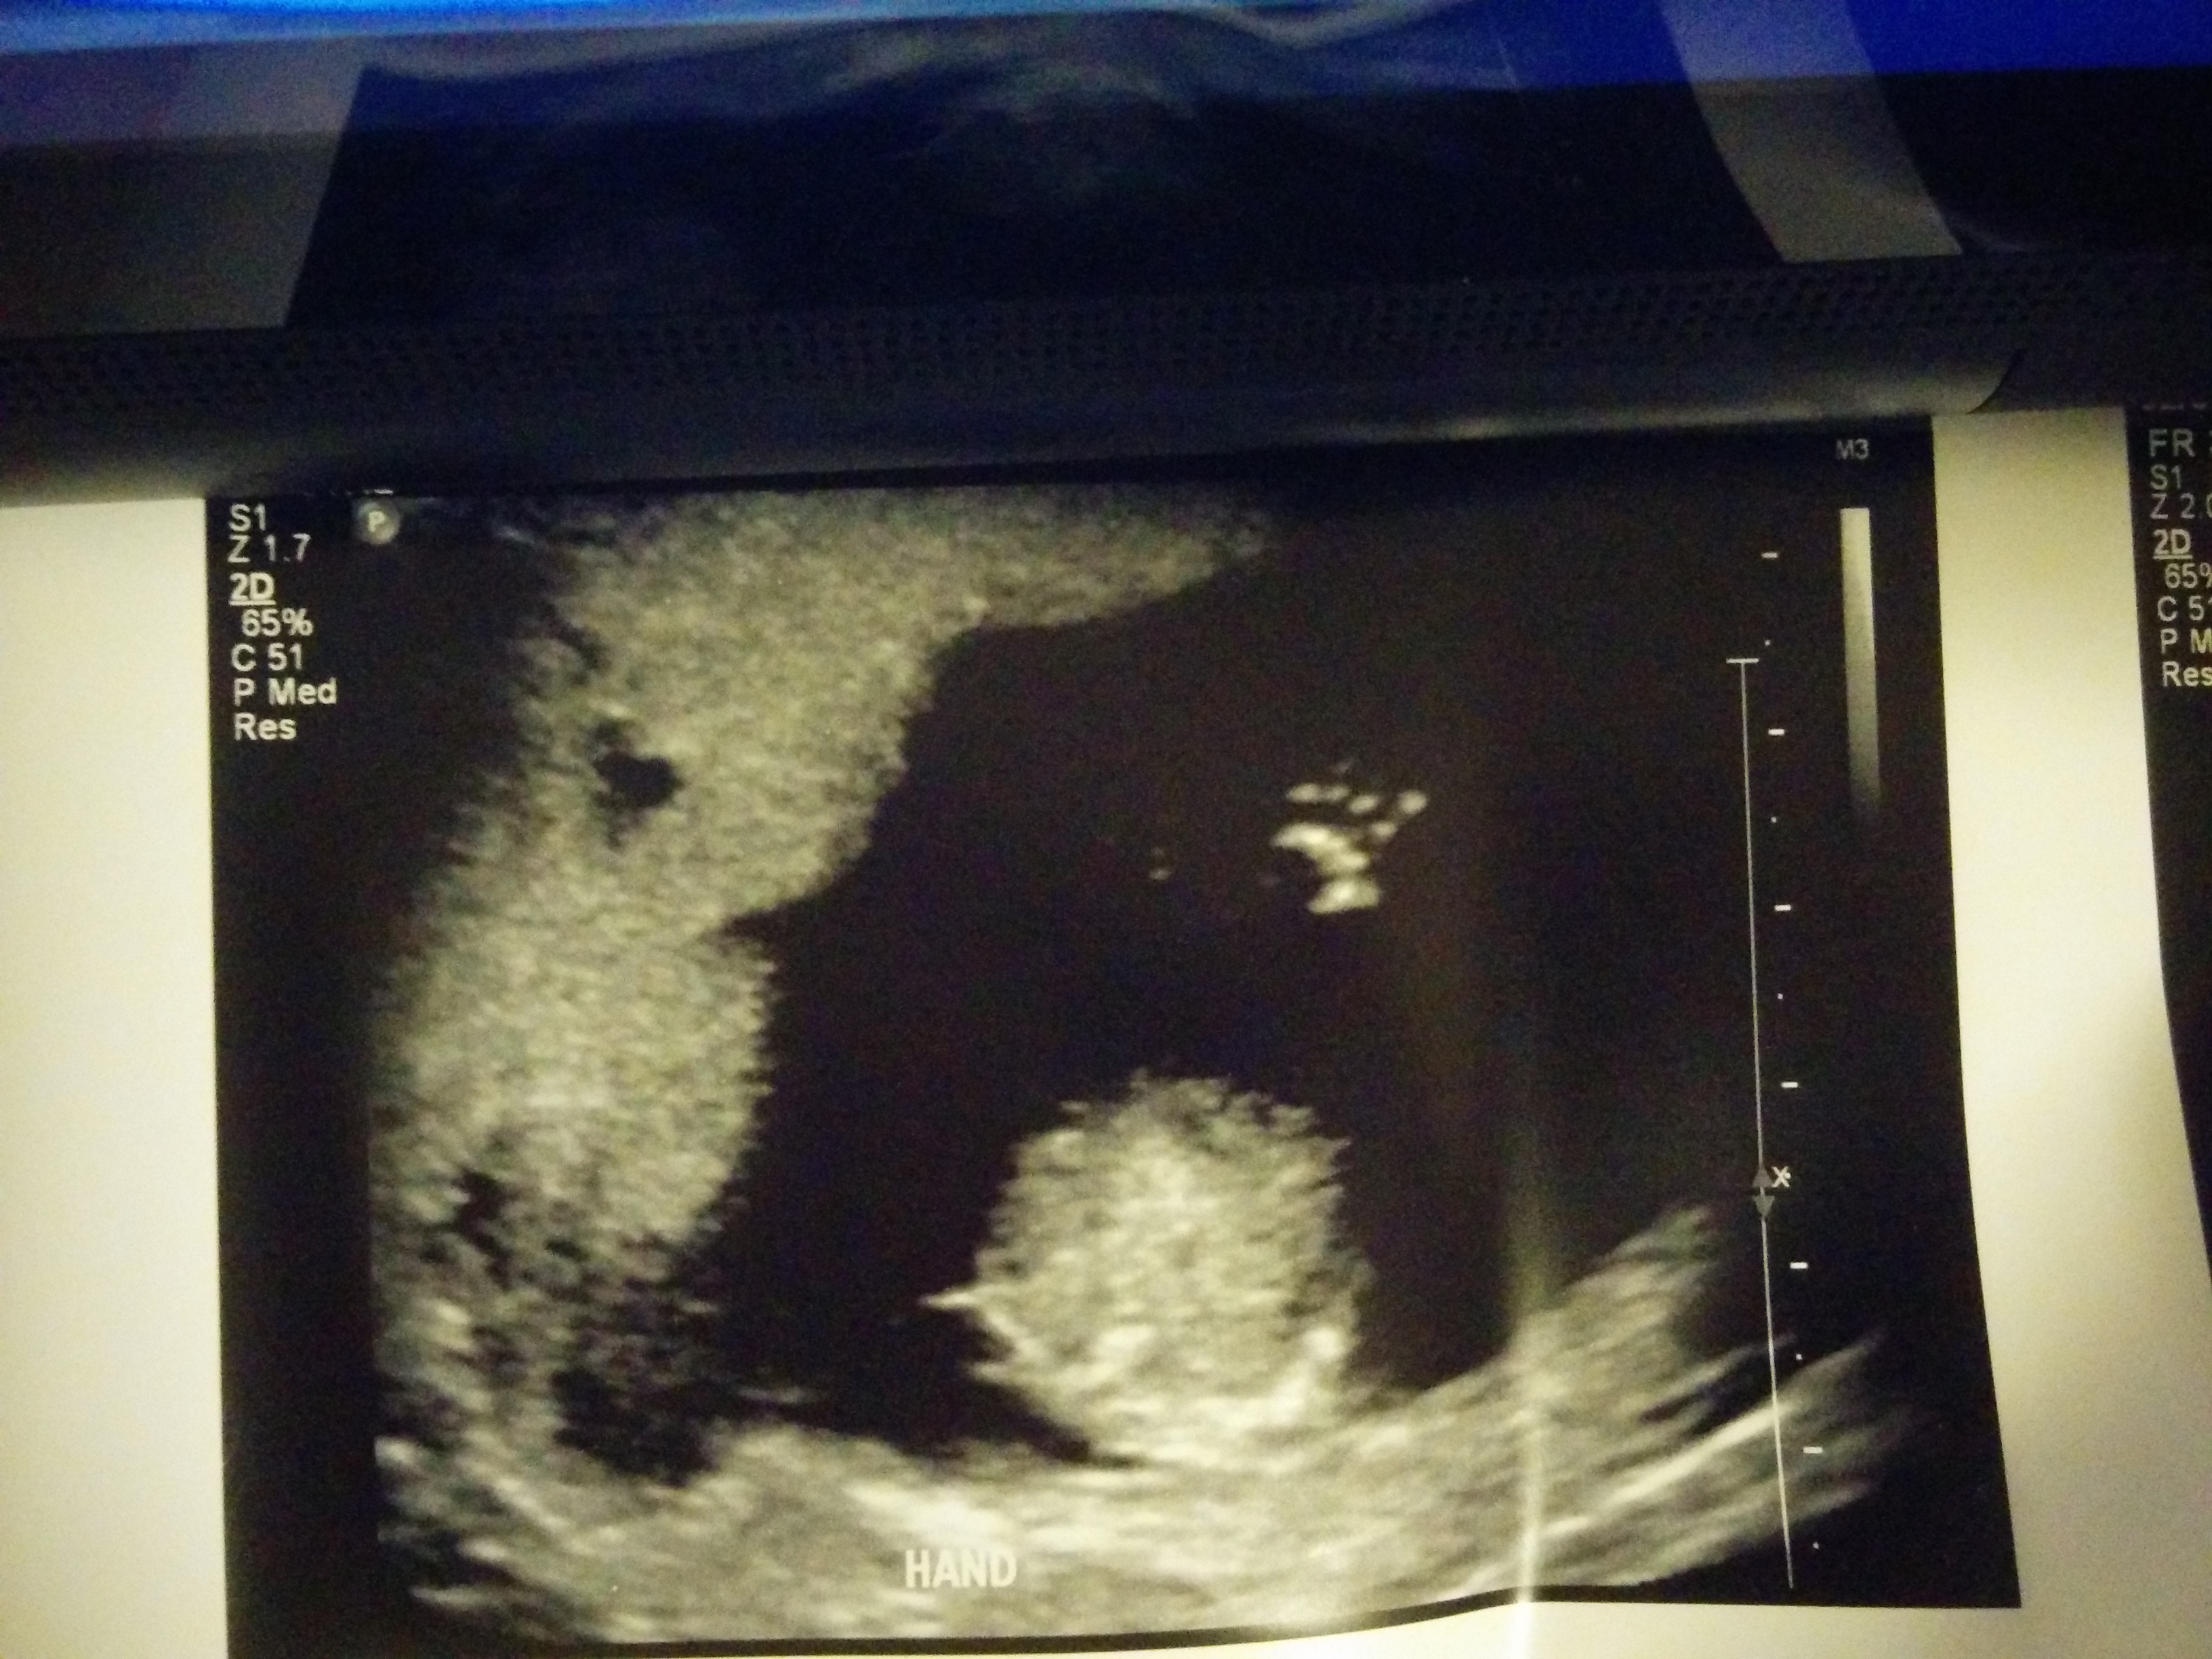

Can anyone see the gender?Attachment 35463Attachment 35464Attachment 35465Attachment 35466

If this is above 12 weeks gestation, I say girl. If under 12 weeks, 50/50 :)

Girl x

girl lean